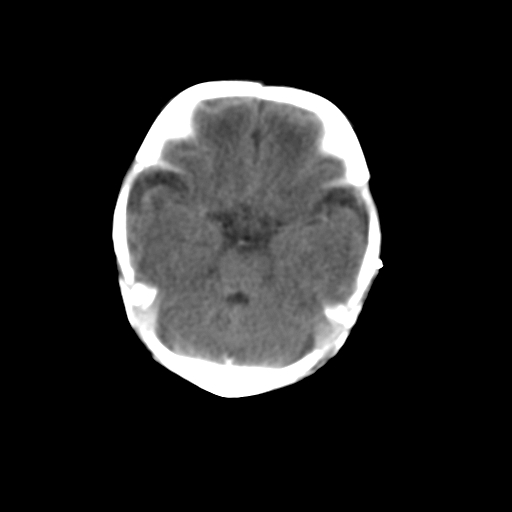

新生儿女2天,有窒息史,经抢救好转!白质最低ct值>23hu,请教各位老师:是否有出血?是否合并缺氧脑病?谢谢!

hie、蛛网膜下腔出血,皮下血舯。

hie、蛛网膜下腔出血,皮下血舯。透明隔间腔形成支持

双侧额叶白质低,白质ct值低于18hu可以考虑水肿改变

后纵裂密度高,前纵裂密度低,比较来说应该考虑有蛛网膜下腔出血

空三角征,蛛网膜下腔出血。